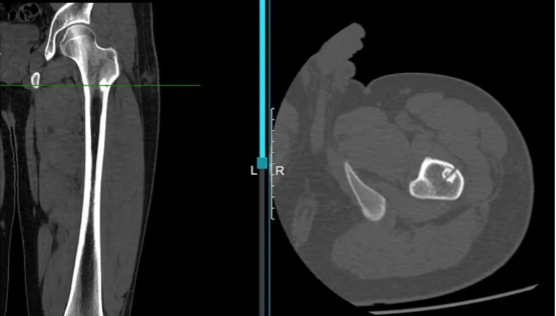

图4:术后CT复查,瘤巢消融位置

入院后诊断为中心型股骨髓腔骨样骨瘤,本型临床症状不如皮质型明显,部分患者疼痛隐匿,单纯射频消融效果较好。入院后第二天全身麻醉后导航下行左侧股骨病灶射频消融术,选择消融针尺寸为15毫米,消融时间11分30秒。术后第二天患者自诉原有疼痛不适症状缓解90%。术后复查MRI可见骨内明显的椭圆形消融范围,精准对应了23*19毫米的消融范围。